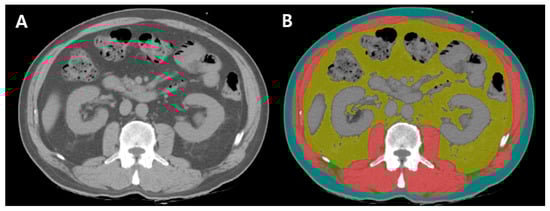

Skeletal muscle area was quantified as the total area of intra-abdominal muscles, utilizing HU thresholds of −29 to 150. VAT area was measured as the fatty tissue within the intra-abdominal skeletal muscles, excluding regions occupied by the kidneys, liver, intestines, and other organs, using HU thresholds of −50 to 150. SAT area was quantified as the fat layer between the skeletal muscle and the abdominal skin, using HU thresholds of −190 to −30. Intermuscular adipose tissue (IMAT) was calculated as the fat accumulation within the intra-abdominal skeletal muscle, using HU thresholds of −190 to −30 (Figure 2) [20].

Figure 2. Cross-sectional CT images at the level of L3. (A) Unenhanced image using Picture Archiving and Communications System (B) body composition parameters classified by color-coded distribution areas using AutoMATiCA (Red, skeletal muscle area; yellow, VAT area; blue, SAT area; green, IMAT area [20].